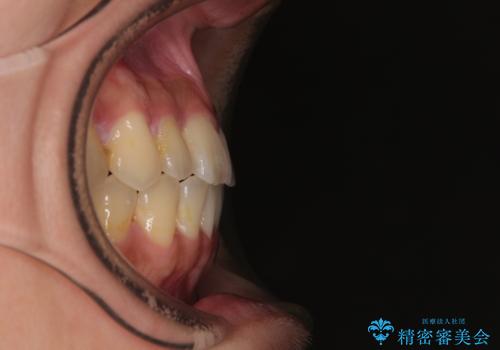

- 上下前歯のデコボコやクロスバイトを気にして来院された患者様です。

上顎歯列が下顎の歯列に対して狭小であり、一部下顎の奥歯が上顎よりも外側に位置している状態でした。

上顎の急速拡大装置を使用して上顎骨を側方に拡大することで上顎歯列を拡大し、下顎歯列も拡大できるようにすることで、歯列を整えることとしました。

歯列矯正では基本的に骨格を改善することはできませんが、急速拡大装置(MARPE)を使用することで上顎骨を側方に拡大させることができ、咬合状態を大きく改善することができます。